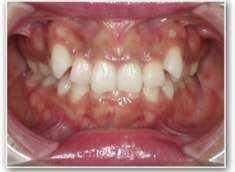

叢生+左下1番先天欠如ケース

治療法:裏側の矯正(リンガルブラケット:舌側矯正)

治療開始1年後